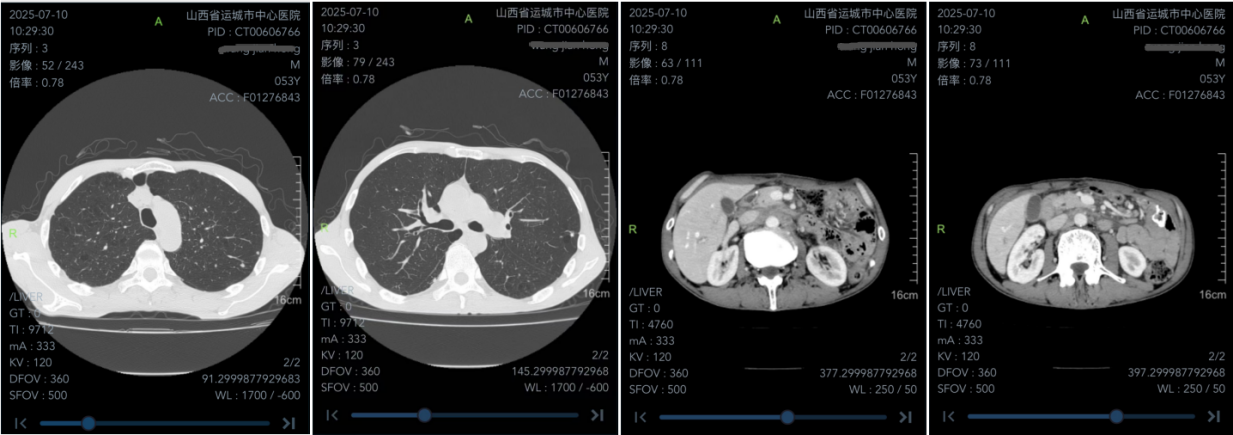

胸部CT(2025年7月,治疗前基线):双肺多发结节,较大者位于左肺上叶舌段,大小约9mm×6mm。右肺下叶见团片状高密度影。胃大部切除伴胃空肠吻合术后,术区可见高密度吻合线影,肝胃间隙及腹主动脉旁可见多发增大淋巴结。

腹部CT(2025年9月26日):胃大部切除伴胃空肠吻合术后;肝小囊肿;左肾上腺内侧腺瘤可能,较前无变化;肝小囊肿,肝增强扫描静脉期略低密度灶同前。